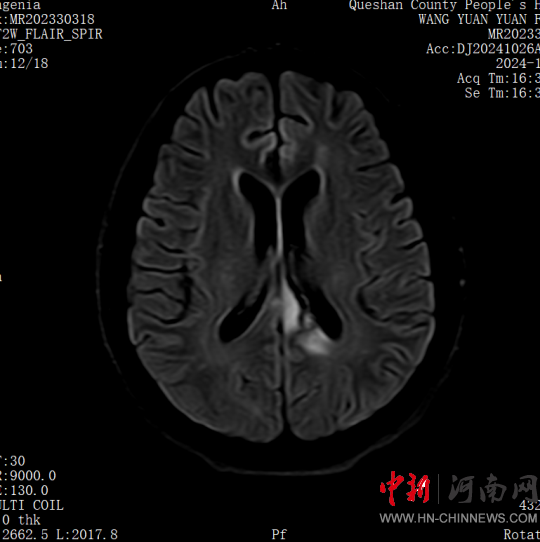

患者,女,32歲,車禍傷,到達(dá)確山縣人民醫(yī)院急診科創(chuàng)傷中心救治時(shí)血壓80/45mmHg,心率115次/分,處于昏迷、休克狀態(tài),病情危重。急診科迅速啟動(dòng)創(chuàng)傷中心急救綠色通道,醫(yī)護(hù)人員立即展開搶救,積極抗休克治療的同時(shí),聯(lián)系神經(jīng)外科、胸外科、急診重癥監(jiān)護(hù)室緊急會診,同時(shí)快速CT、床旁FAST檢查明確診斷。通過一系列急救措施,患者的休克狀態(tài)稍微好轉(zhuǎn),經(jīng)多學(xué)科會診后明確診斷為:多處損傷并失血性休克、彌漫性軸索損傷、蛛網(wǎng)膜下腔出血、腦挫傷、股骨及脛腓骨粉碎性骨折、多發(fā)肋骨骨折并肺挫傷、腰椎骨折。ISS評分高達(dá)50分,死亡率極高,患者病情危重,立即送入急診重癥監(jiān)護(hù)室進(jìn)行高級生命支持治療。